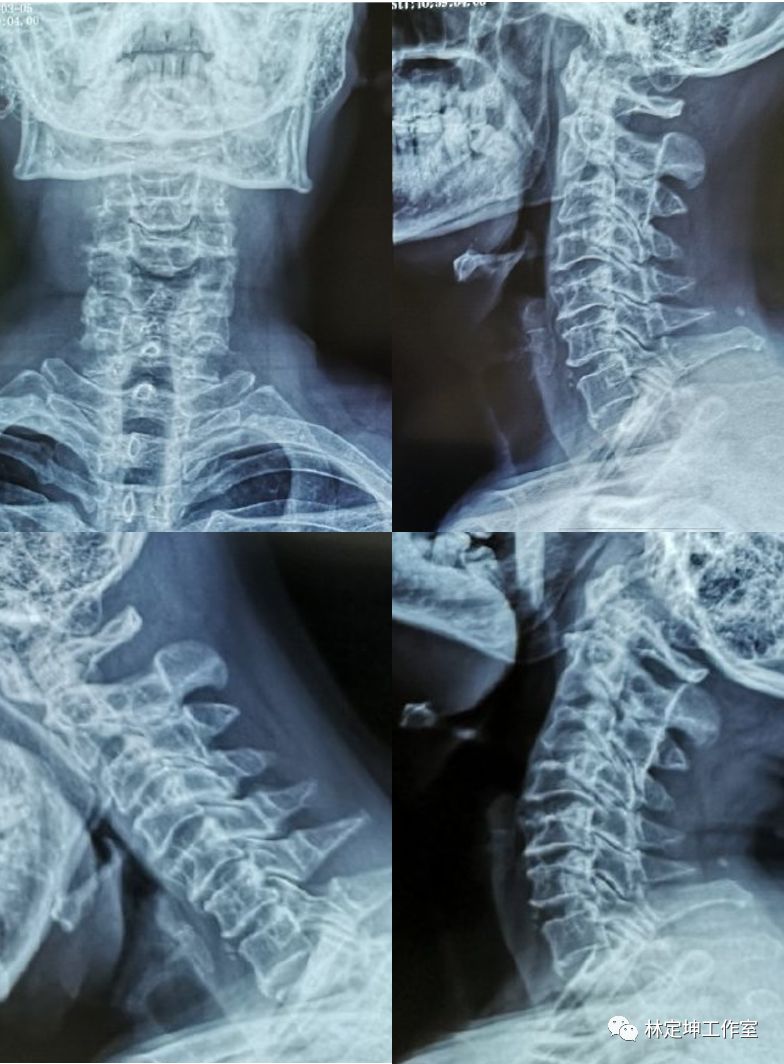

他的颈椎X光照片,显示颈椎骨质轻度增生,但椎节稳定,无发育性椎管狭窄,椎间隙也正常。

张先生的颈椎X线片